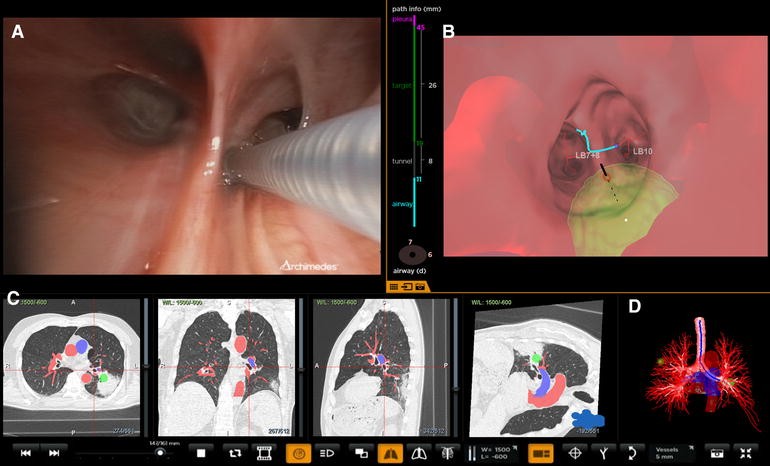

Bronchoscopic transparenchymal nodule access (courtesy Broncus Archimedes™). a Real-time bronchoscopic image showing catheter at the point of entry. b Real-time virtual image with point of entry overlaid. Green area indicates target lesion. The vertical colored lines on the left of the virtual bronchoscopy indicate the distance in the airway, tunnel length, size of the target and distance from the pleura. c Computerized tomography projections with target and vessel overlay. Red and blue colors indicate vessels. The target is marked green. d 3D reconstruction of the airway tree